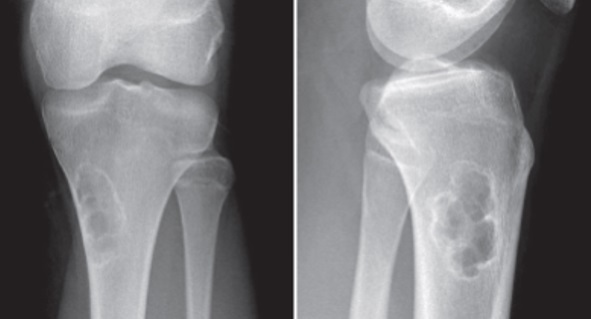

3

Q

Qual diagnóstico?

A

Tela de galinheiro

Dx: condroblastoma